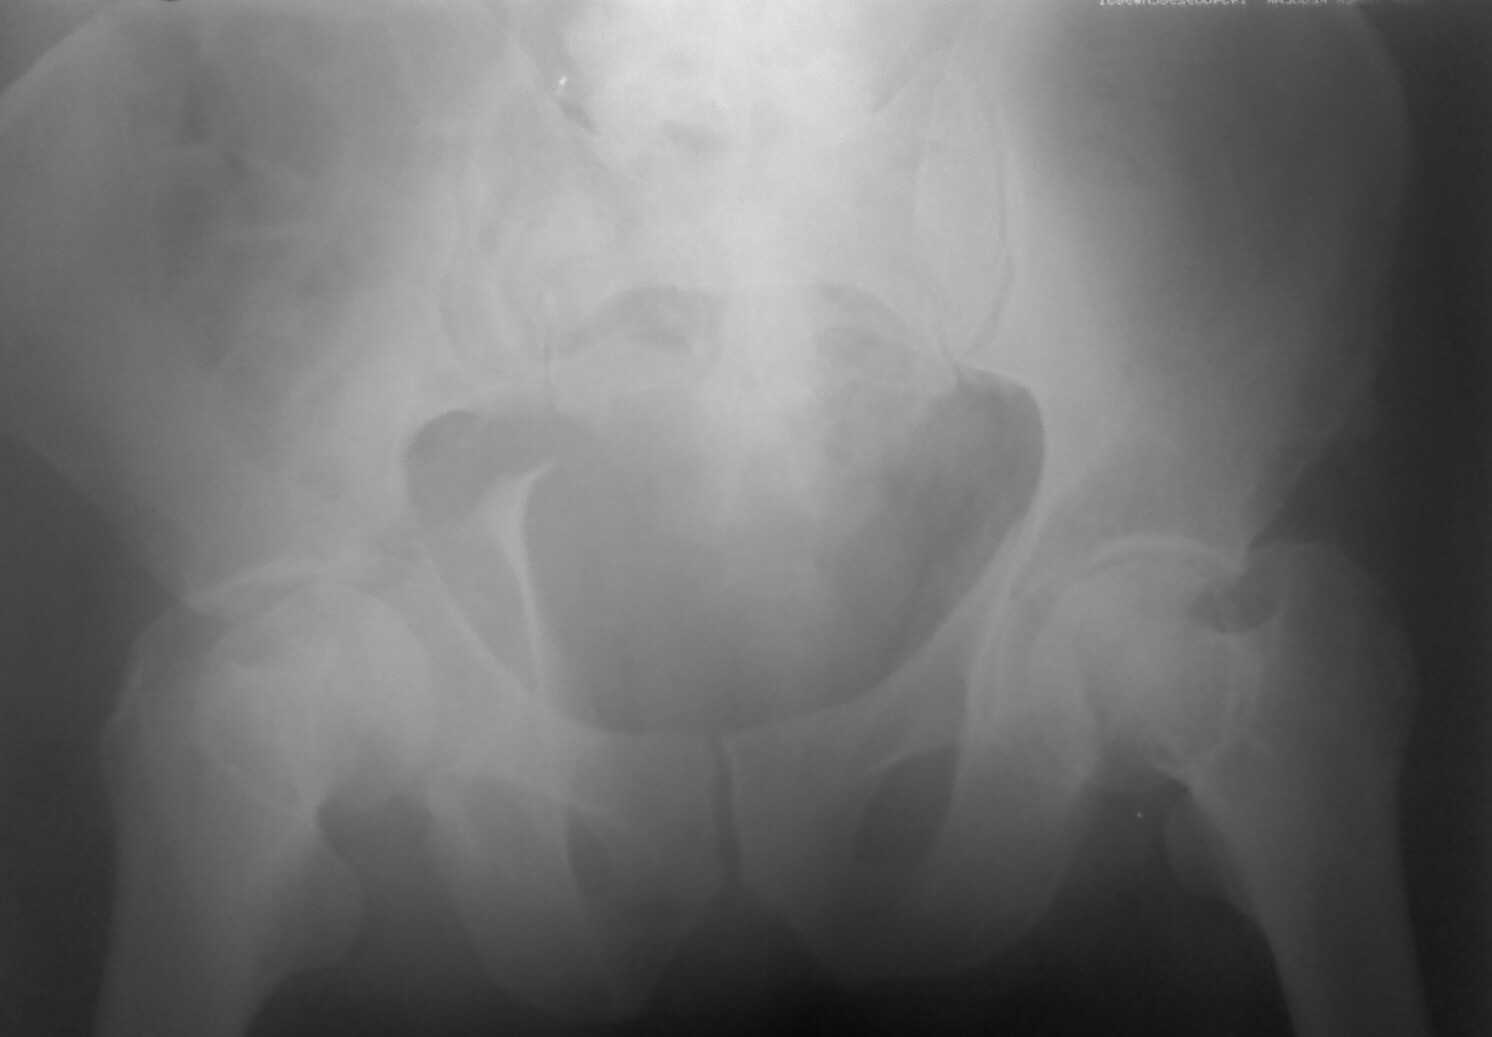

Добрый день ув.коллеги. Теперь подробнее.В нашем отделении находится пациент с тяжелой сочетанной травмой (множественные переломы ребер, тупая травма живота с повреждением печени, селезенки) с нашей стороны тяжелая травма таза.С момента травмы прошло 3 недели.при поступлении в экстренном порядке пациентом занимались хирурги, затем проводилось интенсивное лечение в реанимации. сначала боролись с двухсторонним гемопневмотораксом, потом с пневмонией. В течении всего времени пациент находился в положении по Волковичу, других мер не принималось (почему не знаю). На сегодняшний день состояние больного стабильное, удовлетворительное.пневмония разрешилась, проблем по животу и легким нет, по анализам компенсирован. На представленной R-мме и КТ если я правильно расценил: справа имеется полный внутрисуставной двухколонный перелом, низкий вариант(С2)., слева поперечный перелом вертлужной впадины(В10) без смещения.(извините за качество, снято с телефона)Хотелось бы услышать ваше мнение, предложения по поводу лечения перелома костей таза. Стоит ли оперировать левую вертлугу? Чем предпочтительнее зафиксировать перелом справа? Заранее спасибо. С ув.Андрей.

Извините, пробую еще раз

сделать стандартные проекции Judet и отфотографировать их в лучшем качестве, увеличить микропленку, выложить срезы на уровне свода вертлужных впадин.